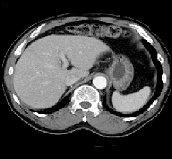

Automatic extraction of liver region from CT-images

We propose a method of automatic extraction of liver regions and its volumetric measurement by computer employing a set of abdominal CT images of a patient.